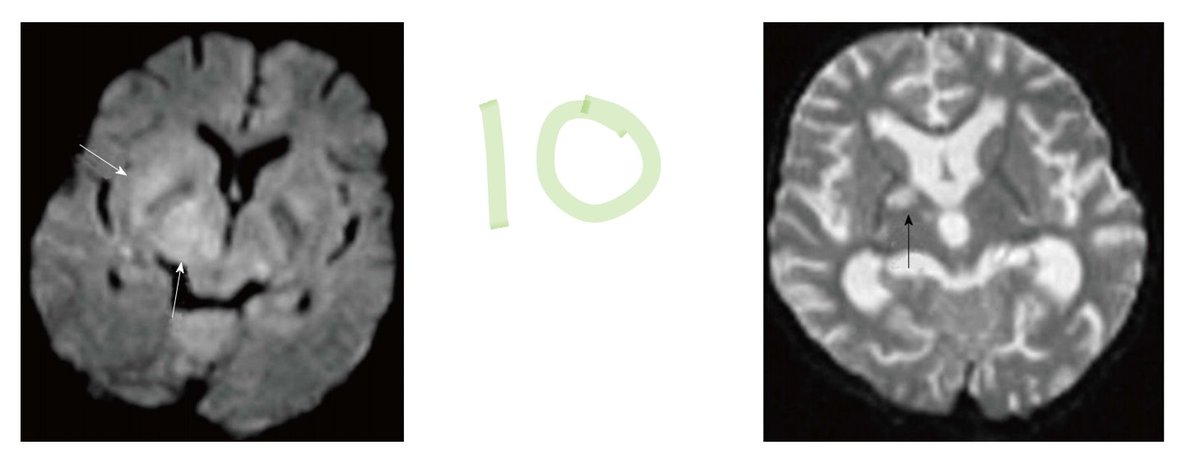

Basal ganglia SOL etiologies:

10: Cryptococcosis, no Gd enhancement, DWI restriction. ImageImageImageImage